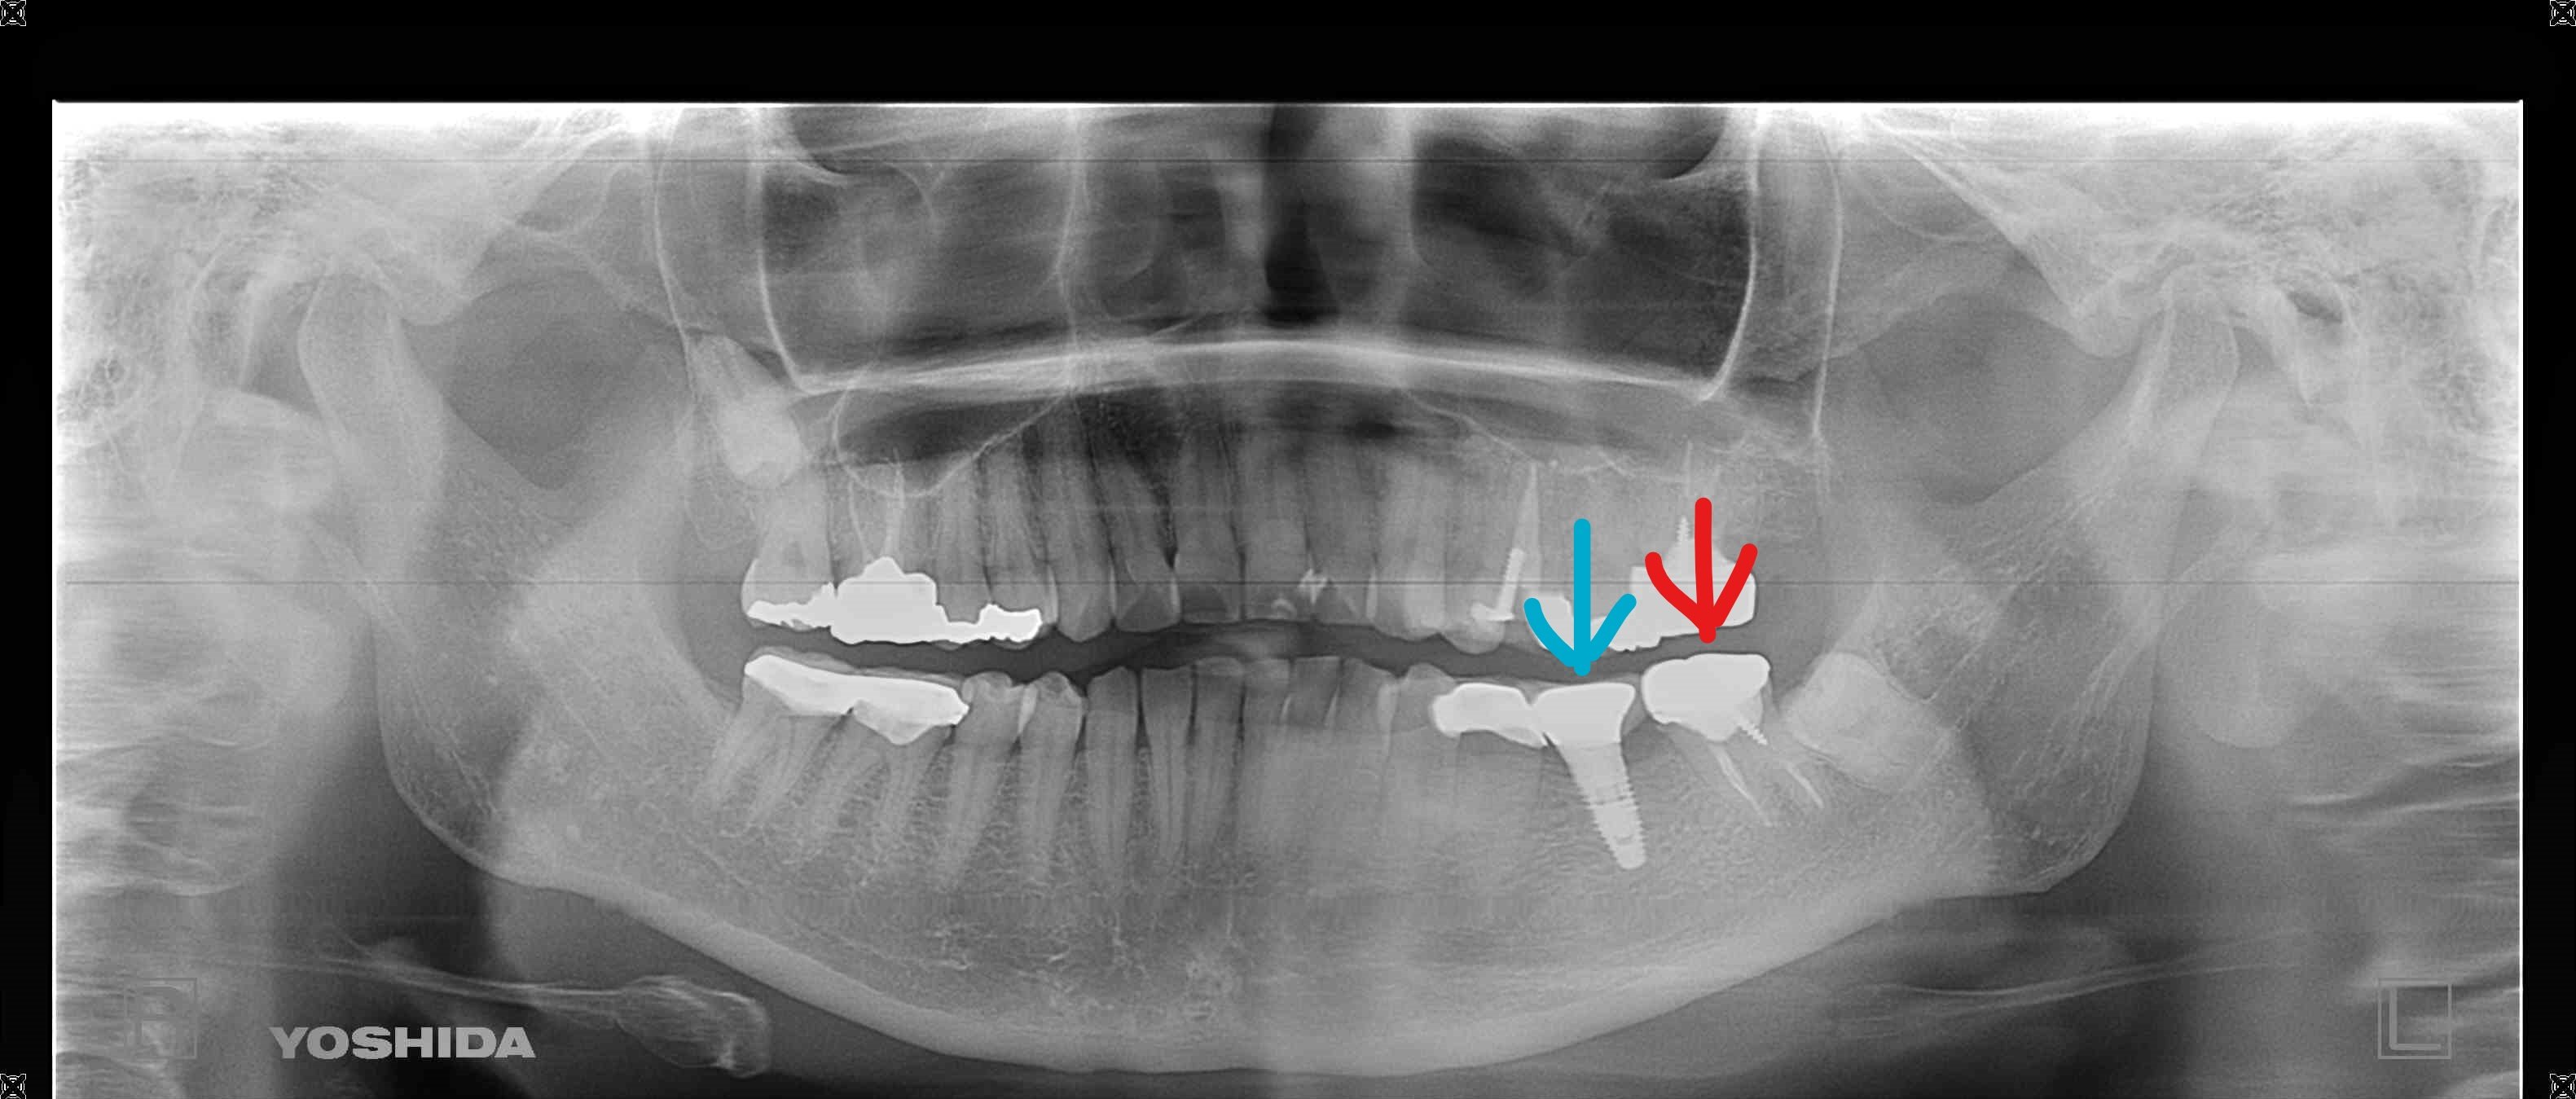

その後、患者さまは「隣接歯に負担のかかるブリッジや入れ歯ではなく、インプラントによる治療を希望」され、左下奥歯部にインプラントとセラミック冠(メタルボンド)を用いた治療を実施しました(右下の写真参照/水色矢印部)。

メタルボンド冠は、セラミック製の外装を持ち、歯垢(プラーク)が付着しにくい構造となっており、インプラント周囲炎などのリスク軽減にも配慮されています(※個人差があります)。